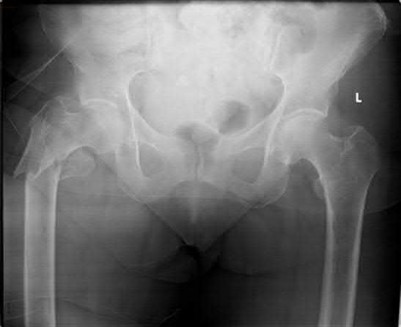

Question 1:

A 35-year-old male is brought to the trauma bay after a severe fall from height. He is hypotensive and tachycardic. An AP pelvis radiograph demonstrates a vertically displaced left hemipelvis with severe disruption of the posterior sacroiliac complex and symphysis pubis. If active arterial hemorrhage is identified on angiography, which vessel is most likely injured in this specific injury pattern?

Correct Answer: Superior gluteal artery

Vertical shear pelvic fractures involve massive disruption of the posterior pelvic ring, including the sacrotuberous and sacrospinous ligaments. The superior gluteal artery exits the pelvis through the greater sciatic notch in close proximity to the sacroiliac joint and is the most commonly injured artery in vertical shear pelvic fractures. In contrast, APC (Anteroposterior Compression) injuries are more typically associated with injuries to the internal pudendal and obturator arteries.